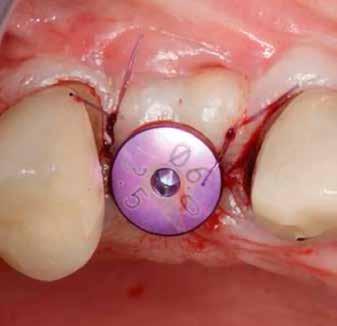

A műtétet követően önkötő akrilátból ideiglenes koronákat készítettünk, amelyeket cementtel rögzítettünk a cirkónium-dioxid ideiglenes fejeken (CR Zi Pillar®, 7. a–c ábrák ).

Protetikai beavatkozás

A végleges protetikai ellátást három hónappal az implantációt követően kezdtük meg. Az implantátumok gyógyulása panasz- és tünetmentes volt. Hagyományos, zárt kanalas A-szilikon lenyomatot vettünk (8. a–c ábrák). Egy esetben a gingivális emergenciát sikerült nagy pontossággal lemintázni fényre kötő folyékony kompozit segítségével (Master Flow, Biodinamica; 9. a–c ábrák). Három lítium-diszilikát és egy monolitikus cirkonkorona készült (10. a–b. ábrák), amelyek cementtel rögzültek a végleges protetikai fejeken (Dual RelyX™ U200, 3M; 11. a–b ábrák).

20. ábra: Jelen esetben – okkluzálisan – egyetlen oszteoszintézis csavart használtunk.

21. ábra: A hangár technika okkluzális nézetből. – 22. ábra: A posztoperatív panorámaröntgen, amelyen látszik a jobb felső kvadráns augmentált területe. A hangár technika lehetővé tette az augmentáció és az implantáció egyidejű elvégzését. 23. ábra: A feltárás és a gyógyulási fej behelyezése. – 24. ábra: A feltárást követően készült panorámafelvétel, amelyen a gyógyulási fej látható.